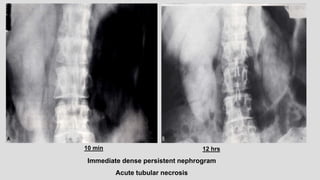

Immediate dense persistent nephrogram

Acute tubular necrosis

10 min 12 hrs